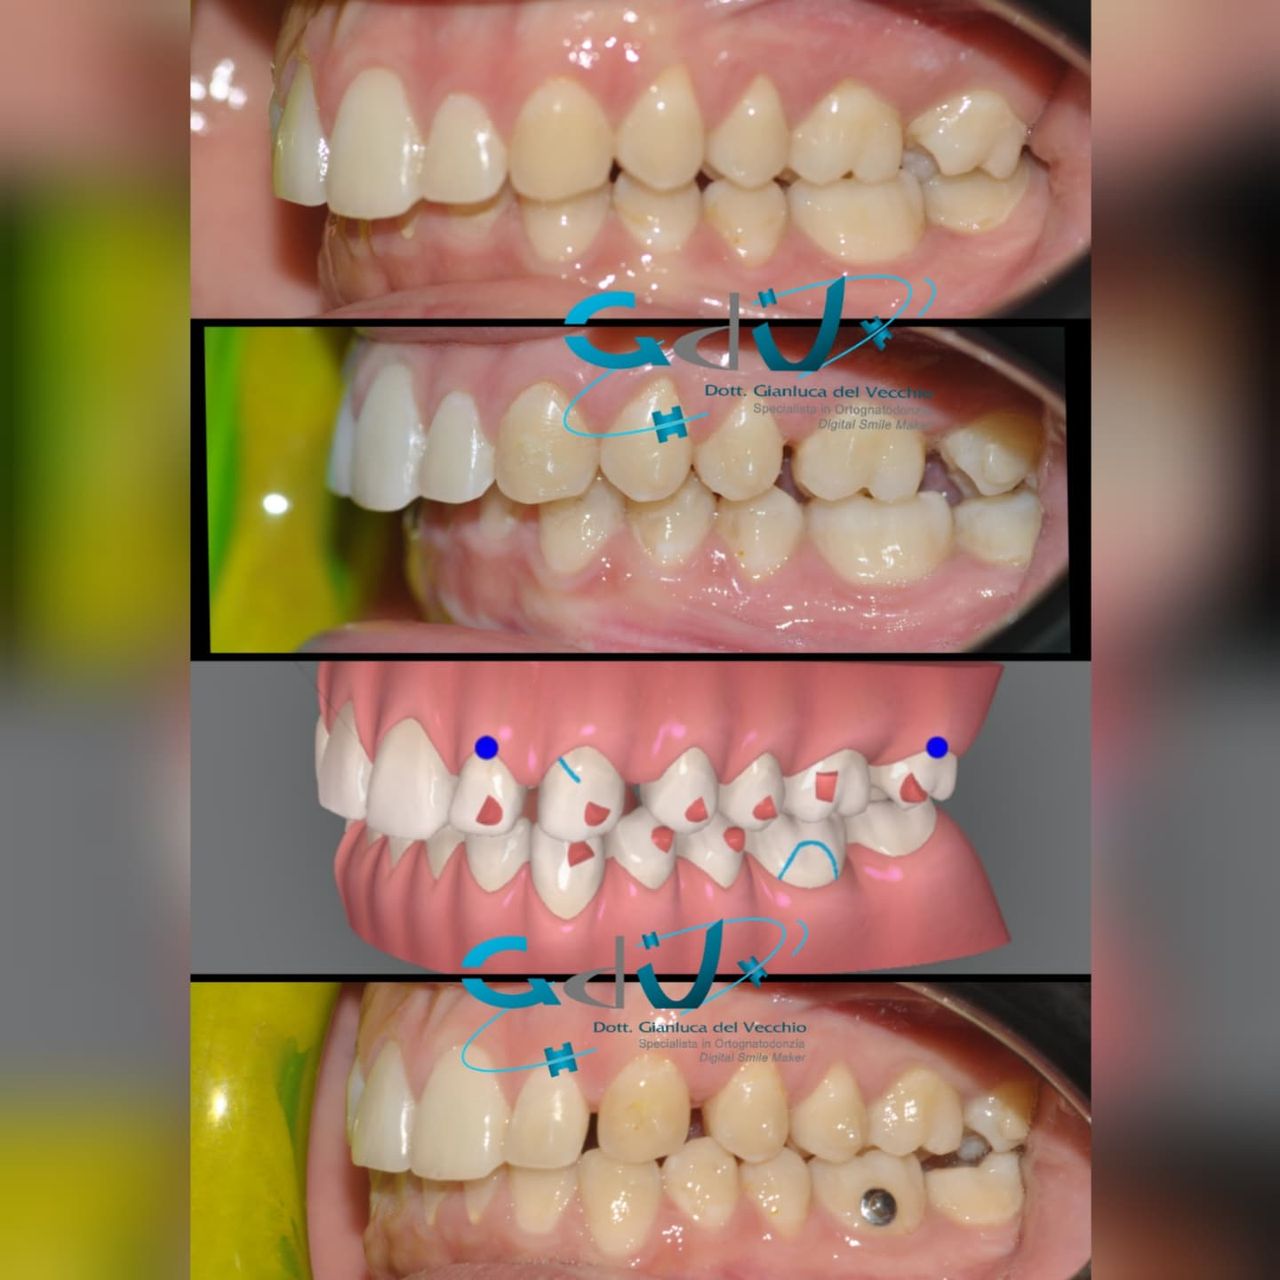

Il dottor Gianluca del Vecchio si occupa esclusivamente di ortognatodonzia, grazie anche alla collaborazione multidisciplinare di una équipe davvero entusiasmante e all’utilizzo di strumenti diagnostici e terapeutici all’avanguardia in ortognatodonzia. Particolare è la sua capacità di condurre i giovani pazienti ad affrontare, nella massima sicurezza emotiva e clinica, qualsiasi eventuale condizione di dolore derivante, ad esempio, da carie o da altre patologie, ma soprattutto di risolvere tutte quelle condizioni di “denti storti”, così spesso causa di disagio psicologico o di fenomeni deprecabili, quale il bullismo.

L’ortognatodonzia è la disciplina che si occupa dell’ortopedia delle ossa mascellari, interviene sulla crescita delle stesse modificando la posizione dei denti secondo quanto necessario. Così la pedodonzia, la seconda disciplina che si occupa, ma in modo esclusivo, dei bambini, affronta tutte le classiche patologie del cavo orale, quando i pazienti sono in età scolare.

Queste le ragioni che consentono di trattare le malocclusioni, sia dei bambini che degli adulti, con protocolli scientificamente validati come i più veloci, affidabili e confortevoli.